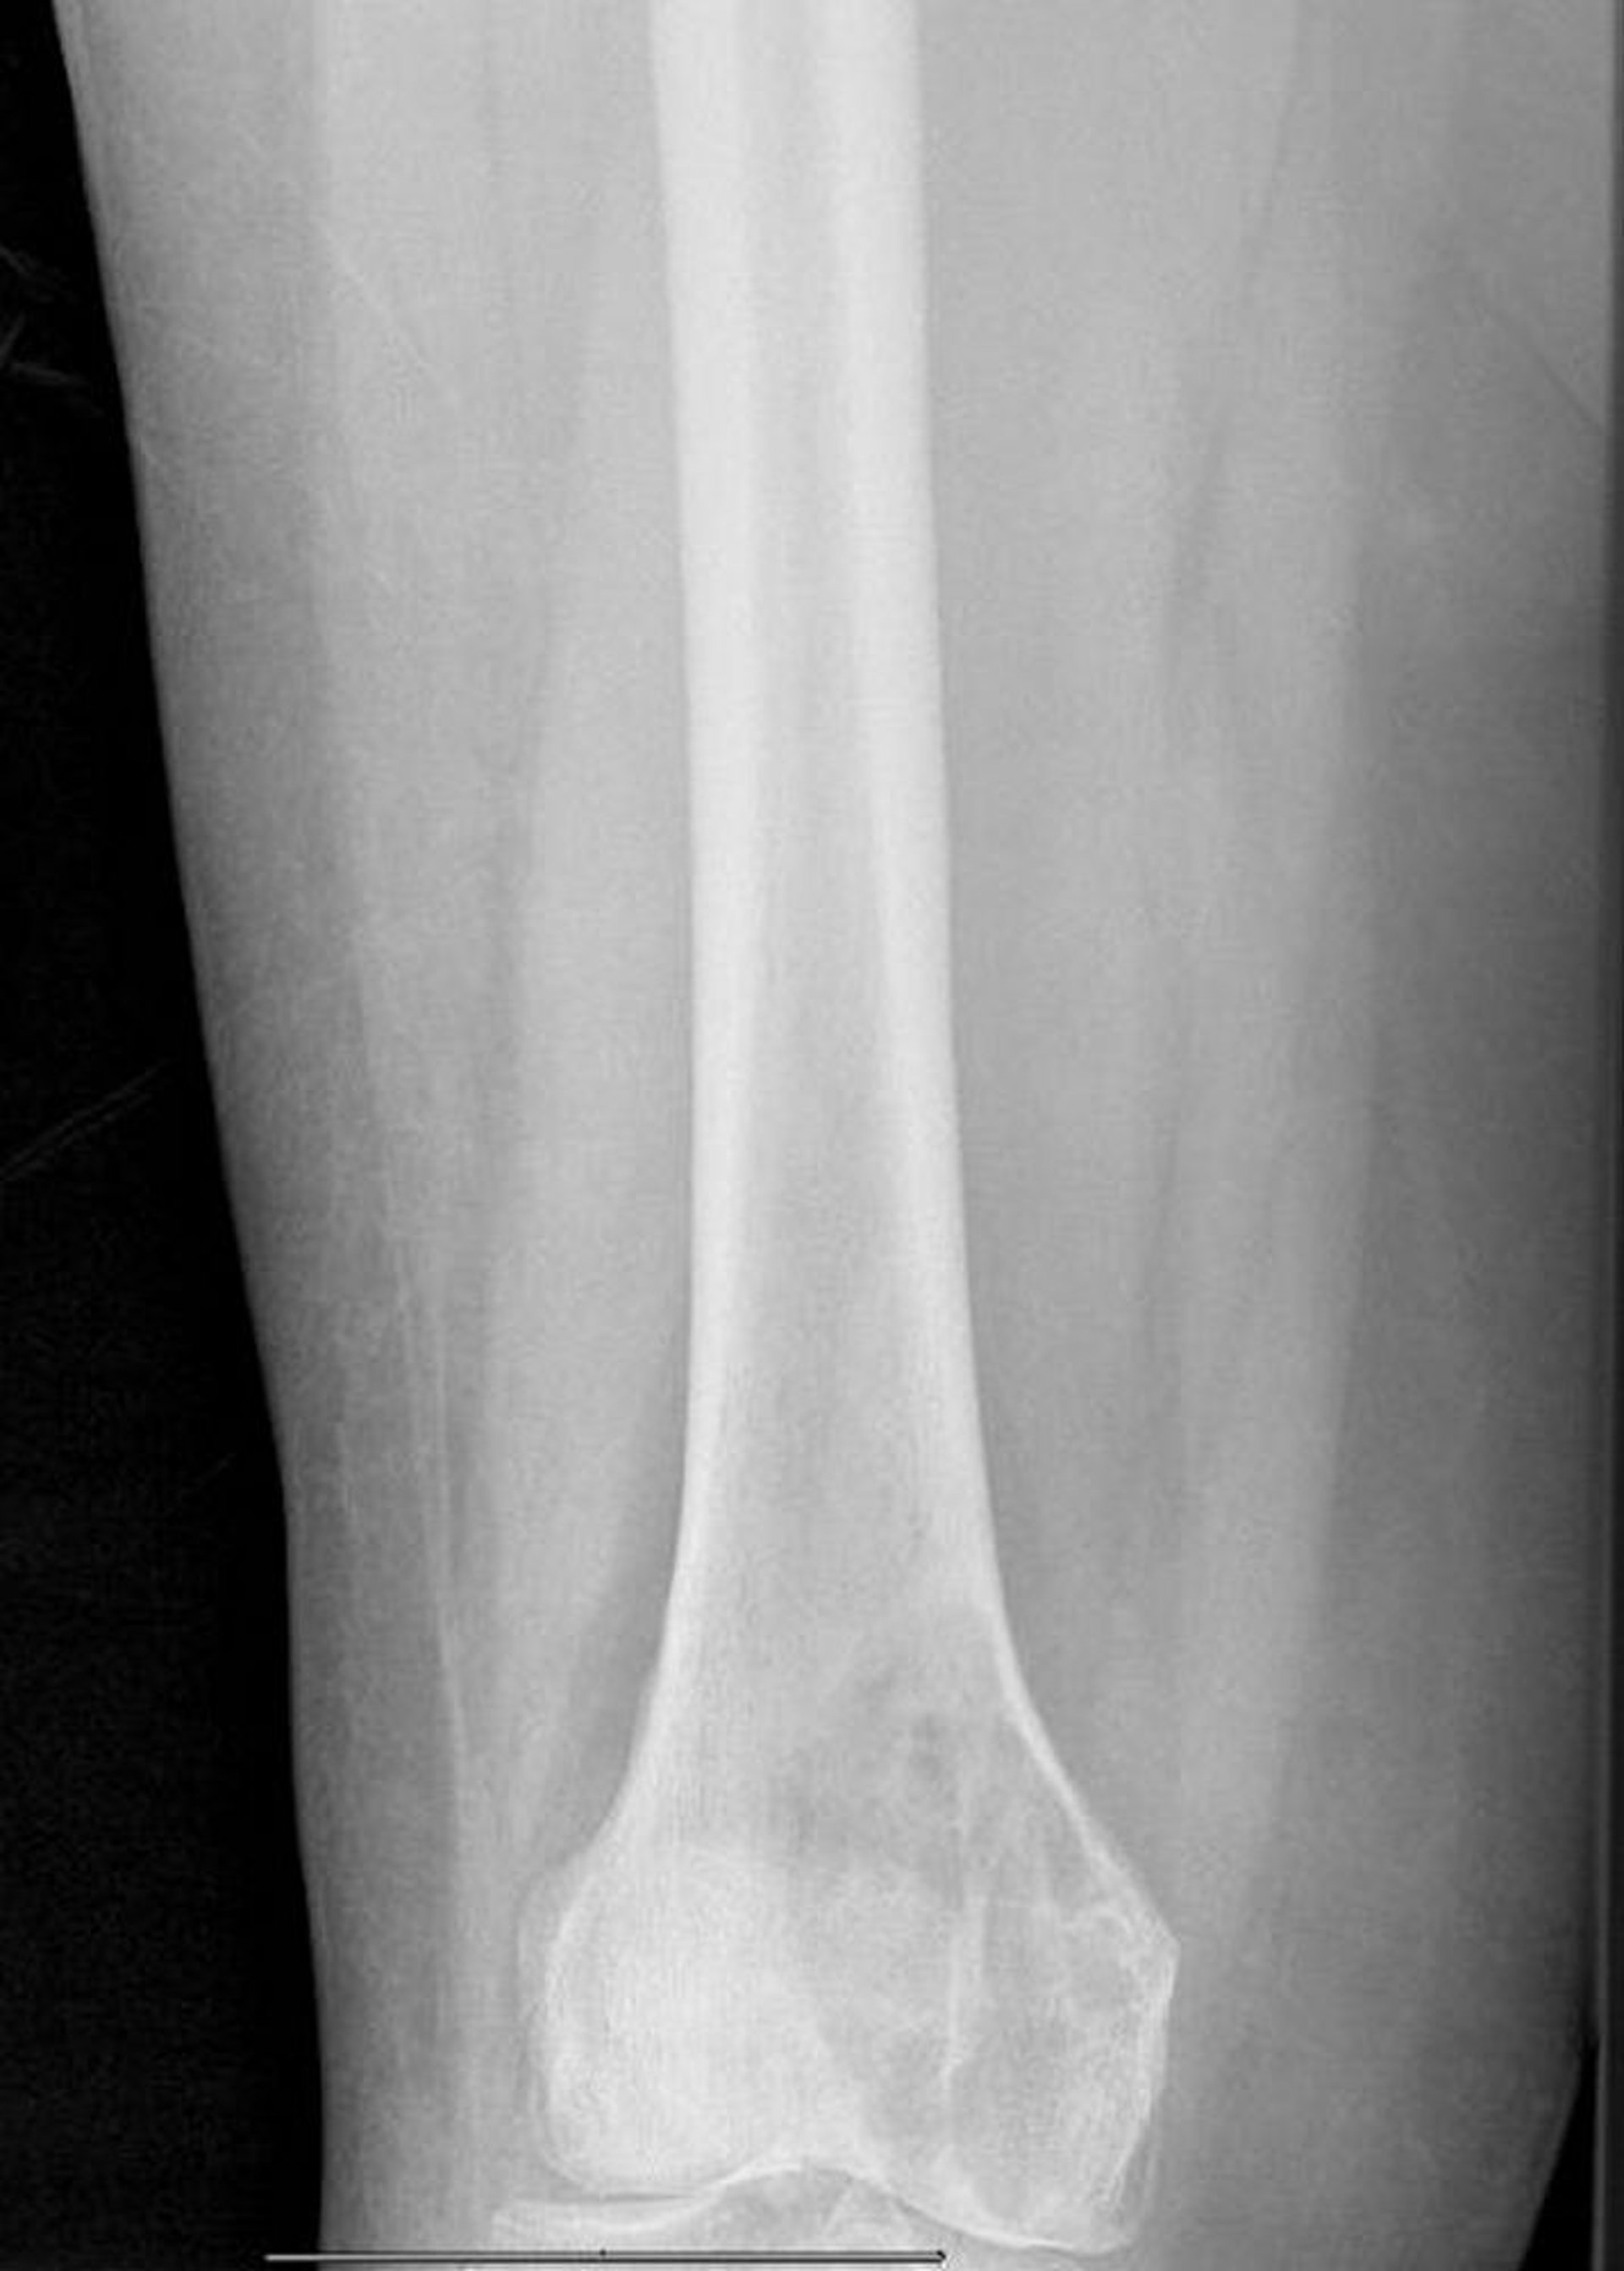

Métastases lytiques du fémur distal

Cette radiographie montre une grande lésion lytique métastatique du condyle fémoral médial avec fracture pathologique imminente.